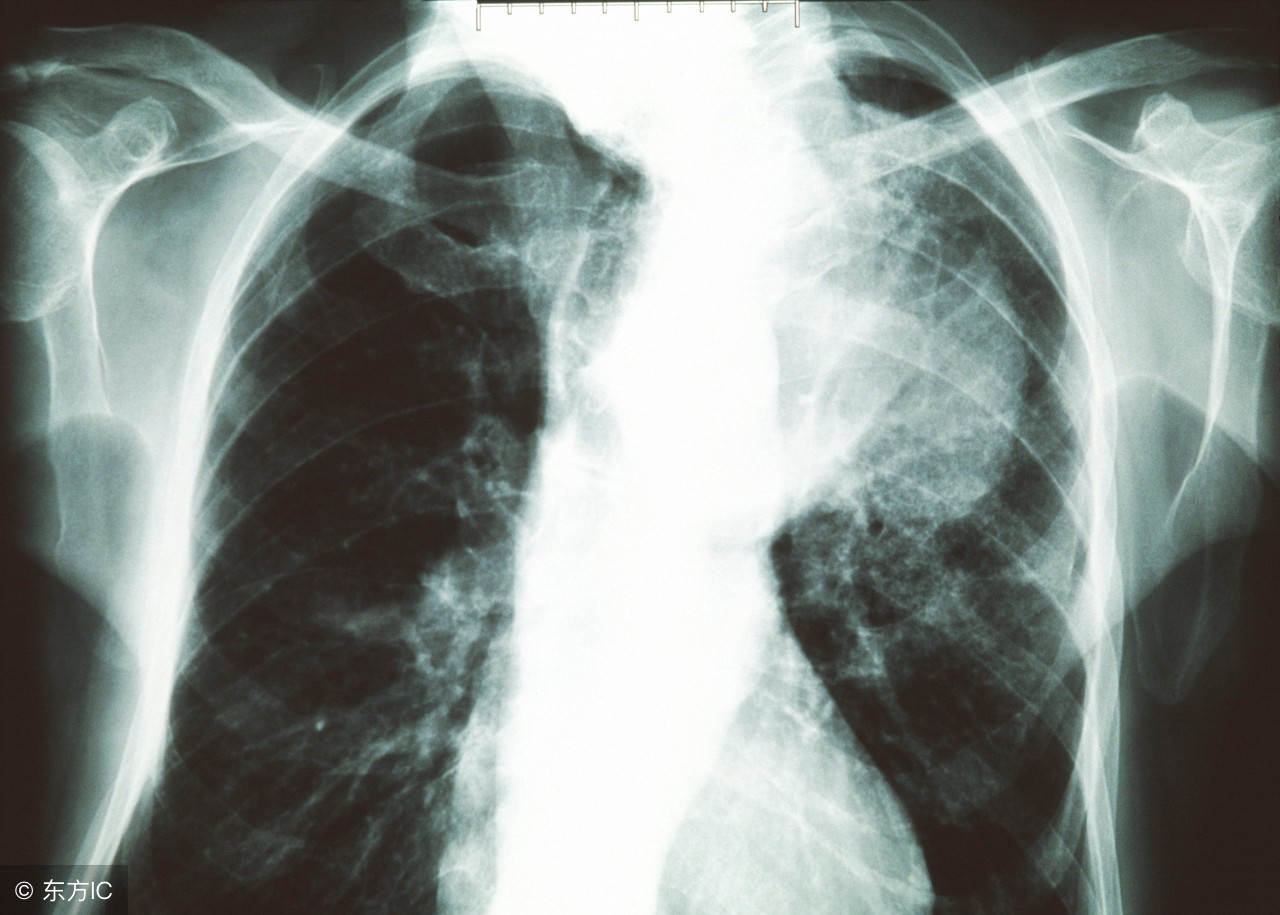

肺癌是一种危害很大的疾病,晚期肺癌不仅影响了生活,而且给患者带来了生理上的疼痛和心理的上折磨,会使人的意志失去战胜困难的信心。今天就给大家介绍一些肺癌晚期的治疗方法。

肺癌又称支气管肺癌,被称为癌中之癌。自工业时代的以来,肺癌的发病率和病死率逐年上涨,且速度极为惊人。对于肺癌晚期患者,其症状是非常明显的,包括肿块、疼痛、气促、咳血、发热等,患者往往承受着难以想象的病痛,对于肺癌晚期症状主要总结为以下几个方面: